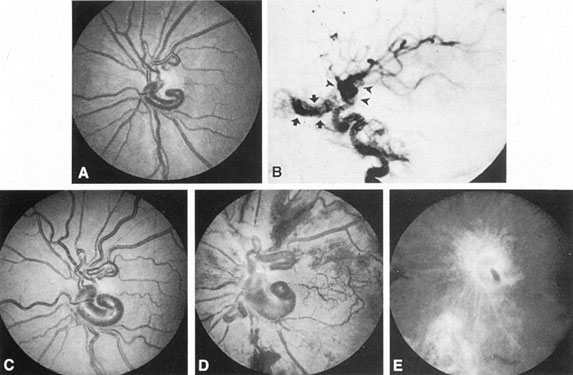

Of particular interest are those AVMs that involve the occipital lobe (Fig. 9). The clinical differentiation of migraine from a cerebral AVM was previously regarded as difficult because the clinical features of occipital lobe AVMs include visual phenomena or headaches. However, in most cases the clinical distinction is possible. In 26 cases with occipital AVM, two distinct syndromes were defined in 18 patients: occipital epilepsy and occipital apoplexy.73 Focal seizures with occipital malformations consist of elementary visual sensations similar to the phenomena evoked by direct cortical stimulations. When seizure activity occurs in the striate cortex (area 17), the patient usually reports sensations of moving lights in the right or left homonymous fields. The sensations are poorly formed, episodic, usually brief, sometimes colored, and unassociated with the angular, scintillating figures so characteristic of migrainous cortical phenomena. Epileptic discharges from areas 18 and 19 cause photopsias that are unlikely to remain stationary and to flicker rapidly. The epileptic photopsias usually last only seconds; occasionally they last for a few minutes before the onset of a generalized seizure. In other instances only the brief visual episodes occur without spreading to produce a generalized seizure. Momentary dimming or blindness in one or both homonymous fields may be experienced with seizure activity in the occipital areas.

Fig. 9. Carotid arteriogram of an occipital lobe arteriovenous malformation (AVM). Lateral (A) and frontal (B) projections demonstrating a small occipital AVM (arrow). The patient was a 23-year-old woman who presented with severe apoplectic unilateral headache, total left homonymous hemianopia, and mild nuchal rigidity. Despite xanthochromic cerebrospinal fluid, she was initially diagnosed elsewhere as having migraine. An AVM was successfully resected, and a small occipital lobe hematoma was removed.

Occipital apoplexy results from hemorrhage and hematoma formation within the occipital lobe and is characterized by sudden severe headache and homonymous visual field loss. Homonymous hemianopia is the most important sign produced by vascular malformations of the occipital lobe. Compression and necrosis of visual pathways by an intracerebral hematoma are the principal mechanisms. Usually the hematoma is large and tends to split or dissect longitudinally through the white matter of the occipital lobe. The effects of compression may be reversed by prompt, surgical evacuation of the hematoma.73 With hemorrhage into one occipital lobe, hemianopia in the visual field of the contralateral normal occipital lobe may develop, producing total blindness that can last for several days. The rapidly expanding hematoma may shift the damaged hemisphere anteriorly, or across the midline, with downward herniation of the uncus through the tentorial incisura. This shift compresses the posterior cerebral arteries and accounts for bilateral occipital lobe dysfunction. Arrest of function in the undamaged occipital lobe may be due to an interhemispheral inhibitory phenomenon termed diaschisis. Visual field defects with occipital AVMs are regularly due to hemorrhage and hematoma formation. Congenital arteriovenous malformations can occupy the entire occipital pole (the macular projection area) for decades without producing visual field defects.

Although migraine is often cited as a symptom of AVM, it is extremely rare that classic migraine is mimicked by occipital AVM. None of the patients in the series by Troost et al73 described the 15- to 20-minute episodes that characterize the visual aura of classic migraine. The headaches of AVM differ from migraine in that they are constantly localized to the same side of the head, and intermittent visual phenomena, if present, can persist throughout the headache or even after, whereas in migraine the visual phenomena usually precede the headache. Bruyn74 has reviewed the clinical features of 57 reported and 7 personal cases of AVM, concluding that the migraine of AVM is late onset, nonfamilial, and brief. Rarely, the complete clinical symptomatology of classic migraine can be mimicked by an occipital lobe AVM (see Chapter 16).75 In addition to hemianopia, other visual disturbances can occur after hemorrhage into the occipital lobe, including alexia without agraphia (see Chapter 7).